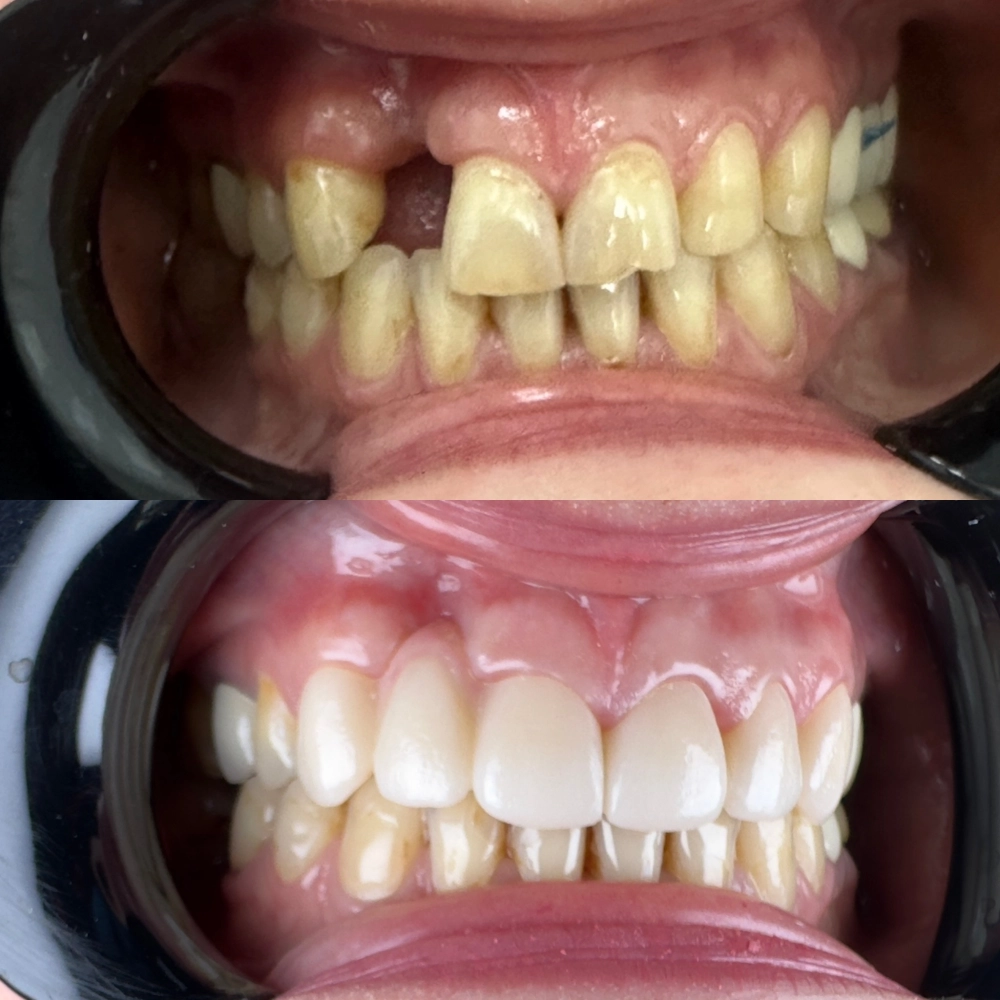

До

После

протезирвание в зоне улыбки (керамические реставрации)